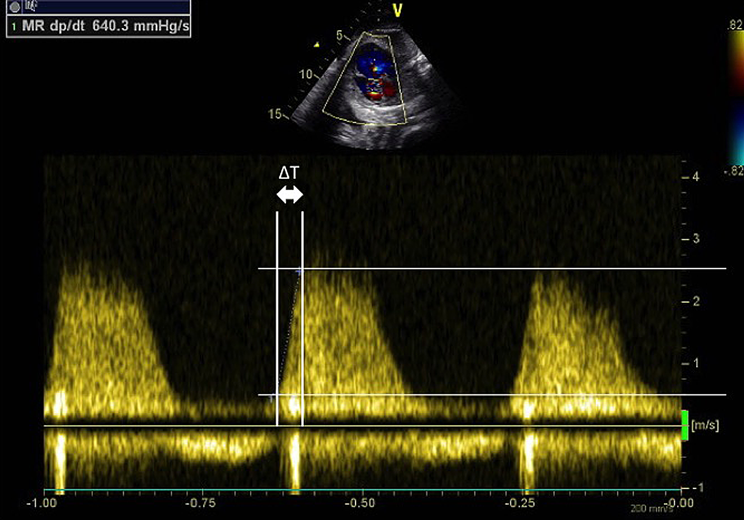

dP/dT

全収縮期にわたる三尖弁逆流が認められる場合には,連続波ドップラーによる逆流波形三尖弁逆流速度の立ち上がりの傾きから心機能を評価する(Fig. 4).心収縮能が保たれていれば収縮期早期に急峻に心内圧が上昇するのに対し,機能低下がある場合には圧の立ち上がりが鈍化する.三尖弁逆流血流速度が0.5 m/secから2.5 m/secまで上昇するのにかかる時間(ΔT)を計測する.三尖弁逆流速度が0.5 m/secから2.5 m/secまで逆流速度が上昇すると,簡易ベルヌーイの式を用いると推定右心室圧は24 mmHg上昇したと考えられ,24 mmHg/ΔTで圧の上昇率を評価する.800 mmHg/sec以下は低値である.400 mmHg/sec以下は重症な収縮能低下と考えられている8)

Fig. 4 Tricuspid regurgitation Doppler waveform of fetal Ebstein disease with hydrops

The time interval between the points at which the velocity was 0.5 m/s and 2.5 m/s (ΔT) was measured, and according to the Bernoulli’s equation, this pressure increase was 24 mmHg. Thus, dP/dt is calculated as 24/ΔT (mmHg/sec).